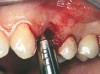

Figure 13  The drill bur was used to start the implant site preparation.

Figure 13

At the time of surgery, the tooth was extracted without harvesting any mucosal flap because the implant site was prepared by means of a pilot drill bur (Figure 13) and alternating osteotomes (Figure 14A and Figure 14B). The implant was positioned and showed primary stability. The implant was loaded 2 days after surgery. Then, splinted PFM crowns supported by custom gold abutments were delivered. At 6 months posttreatment, the radiograph revealed no bone resorption and the clinical result was optimal (Figure 15A and Figure 15B).